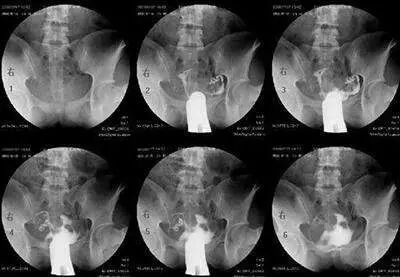

最常用的是输卵管碘油造影(HSG)

医生会根据不孕的时间、可能的原因,来选择是否需要做HSG。

造影的时间一般在月经干净后3天到排卵之前,造影前不要有性生活,白带检查正常等等。造影后1周禁性生活,当月最好不要尝试怀孕。